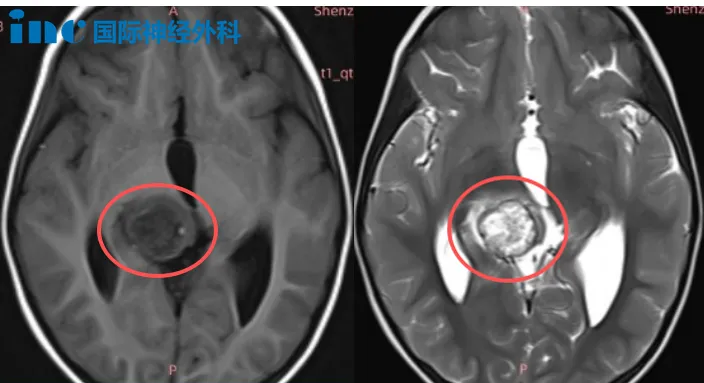

那么,面对此难题,他们如何决策?近期巴教授中国行中,又遇到一例类似患儿。年仅4岁女孩果果,连续摔倒后检查发现右侧丘脑占位性病变,大小约22×21×19毫米;邻近中脑左侧及中脑导水管受压。果果目前虽无显著症状,但仍令父母忧心不已:这是什么性质病变?是否需要手术?若巴教授手术,风险有哪些?体重仅14kg的幼小果果能否承受开颅手术?

巴教授表示:由于肿瘤体积较大并伴明显水肿,当前治疗选择应为手术。因为若盲目进行化疗,缺乏确切病理诊断,没有意义——我们未知肿瘤类型。而对4岁女孩,单独放疗也不可取。

因此,首要步骤是实施手术,获取肿瘤组织,取得明确病理诊断,并进行基因检测。这样才能准确判断后续是否需要额外治疗。另外,单纯等待或观察也不可行,原因有三:肿瘤体积大、水肿明显以及合并脑积水。